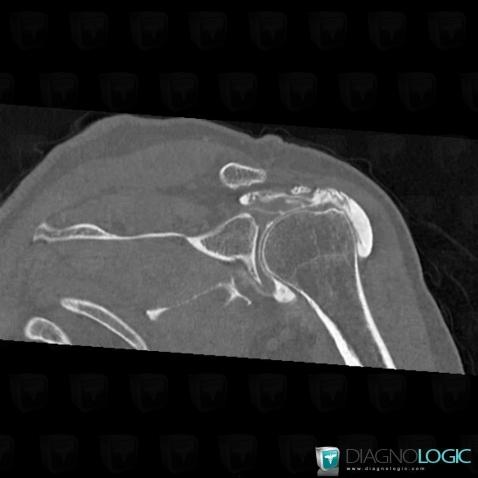

Rotator cuff tears, Supraspinatus tendon, CT

- Diagnosis Rotator cuff tears, Location(s) Supraspinatus tendon, with gamuts